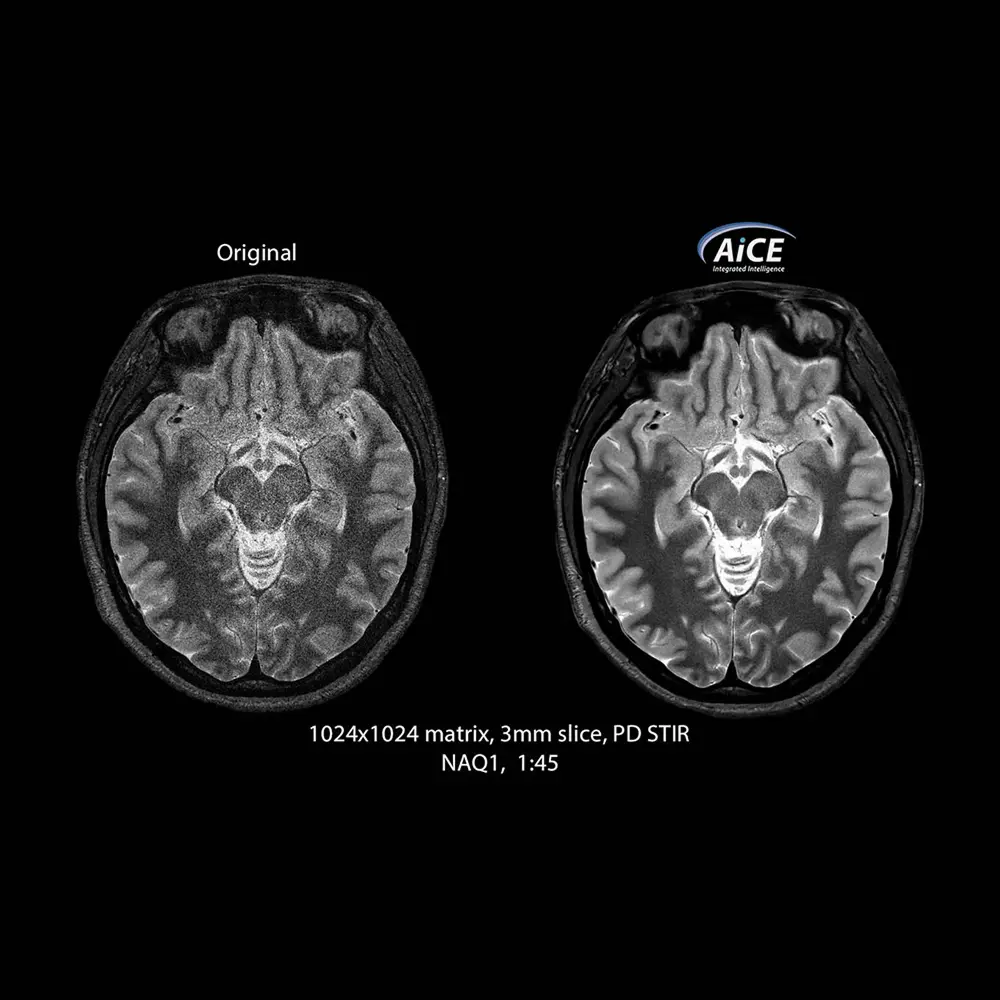

AiCE è la prima tecnologia di ricostruzione al mondo basata sul Deep Learning per la Tomografia Computerizzata. È un’unità di ricostruzione opzionale nei sistemi Canon che rimuove in modo intelligente il rumore dalle immagini CT generando un elevato rapporto S/R e migliorando pertanto la risoluzione anatomica e spaziale. Un algoritmo basato sul Deep Learning riduce il rumore termico generato sull’immagine grazie ad una Rete Neurale di tipo Convolutivo (Deep Convolutional Neural Network, DCNN). La rete neurale è stata precedentemente addestrata a riprodurre immagini ad alta qualità, ottenute ad esempio con un elevato numero di medie, avendo in ingresso le stesse immagini ma caratterizzate da una forte presenza di rumore. In tal modo, AiCE è in grado di ripristinare un alto rapporto S/R in immagini CT acquisite con rapporti S/N bassi (ad esempio acquisite con alti fattori di accelerazione e/o a elevata risoluzione spaziale).